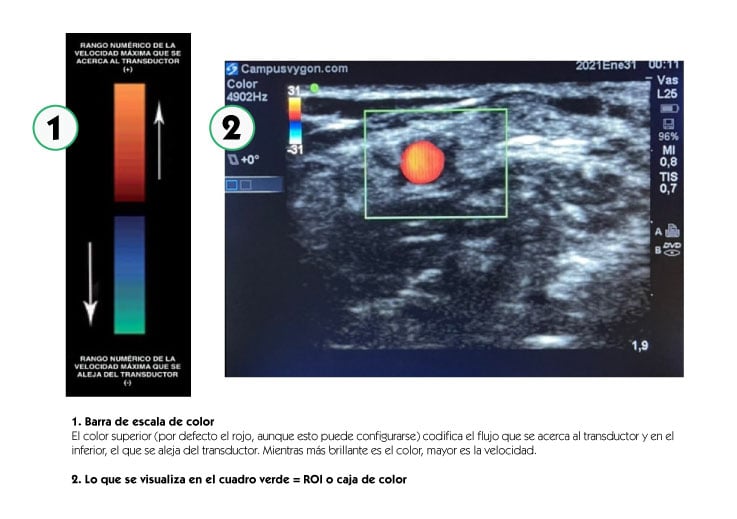

Mediante la aplicación del modo doppler color, se codifica la velocidad media del flujo estudiado, asignándole un color que va a estar determinado en relación con el sentido del flujo, de acuerdo con una determinada escala, superponiéndola a la imagen en Modo B (bidimensional o escala en blanco y negro). El ROI (Region Of Interest: Zona De Interés) o caja de color, determinará la zona de muestreo.

“Es esencial, para obtener una buena señal Doppler color, vascular el transductor y conseguir un ángulo menor de 60º obteniendo una medición óptima con una angulación de 30º o menor”.

Posteriormente, angulamos el transductor entre 30 a 60º o bien hacia la parte distal del cuerpo (hacia la mano), o hacia la parte proximal (hacia la cabeza). Por último, volvemos a activar el modo doppler color para que comience el análisis, obteniendo una tonalidad roja al identificar el flujo que fluye hacia el transductor o azul si éste, se aleja.

En el estudio de las extremidades, si basculamos la sonda de tal manera que los ultrasonidos se dirigen hacia la cabeza del paciente, los vasos que veamos en color rojo serán arterias y los que veamos en color azul serán venas. En la tabla adjunta se muestran las diferentes combinaciones con las que estudiar el capital vascular del paciente con modo doppler color en plano transversal.

Esto facilita la identificación del vaso, sin tener que bascular la sonda en la piel del paciente. Teniendo en cuenta la posición de la muesca del transductor respecto a la pantalla y la angulación del ROI, podremos discernir la dirección del flujo estudiado mediante la misma regla: el flujo que se acerca al transductor será de color rojo y el que se aleja de color azúl.